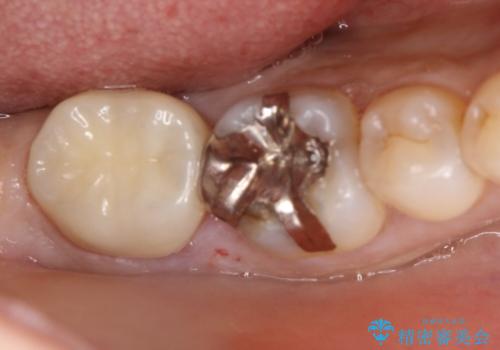

被せものはフルジルコニアクラウンにて行っております。

その後、新しい土台を立て、仮歯に置き換えたのち、フルジルコニアクラウンにて治療を行いました。

患者さんからは、「とてもお口に馴染んで気に入っている」とおっしゃって頂けました。

費用:仮歯1万円、フルジルコニアクラウン7万円(税別)